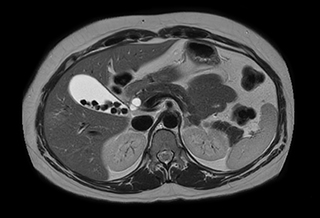

Free breathing abdominal MRI with VitalEye

Ascites can be hard to image, but excellent result is obtained with Ingenia Ambition. This high resolution image demonstrates the high quality that can be obtained with VitalEye and the patient just breathing normally. The acquisition time is fast thanks to the accuracy of the respiratory gating with VitalEye** and it also saves the time needed to put a respiratory belt on the patient.

MCVI VitalEye abdomen

3D T2 with VitalEye

MCVI VitalEye ascites